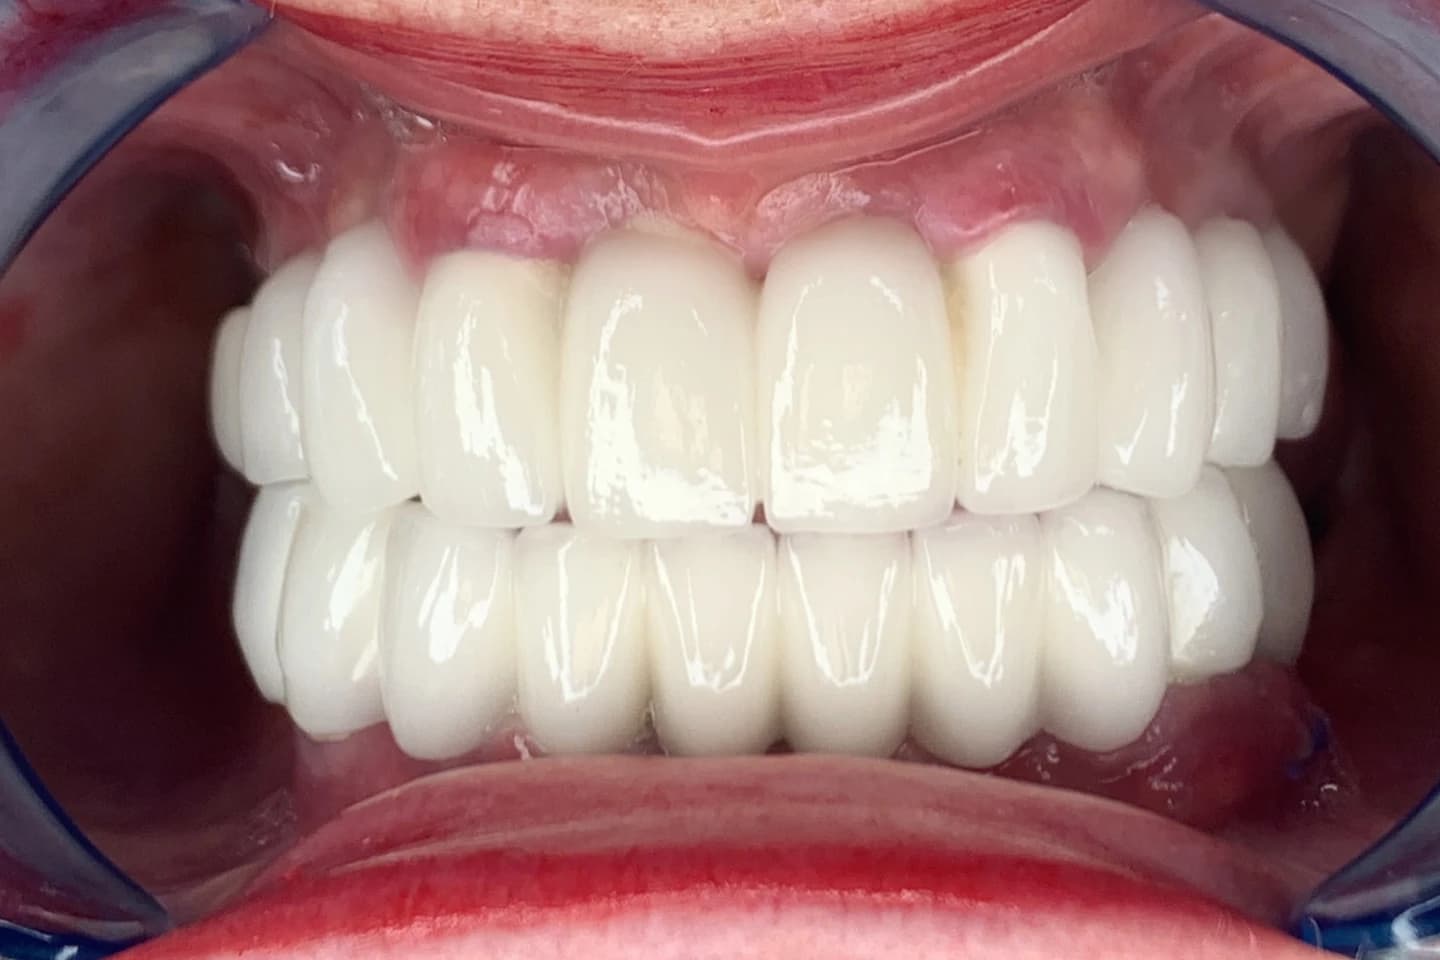

Bezmetalne krunice - pre i posle

- Želite prirodan osmeh bez metalnih ivica? Bezmetalne krunice su idealno rešenje! Pogledajte kako smo transformisali osmehe naših pacijenata.

Cirkonijum krunice - pre i posle

- Cirkonijum krunice - vrhunac estetike i dugotrajnosti. Otkrijte kako ove krunice mogu da vam pruže savršen osmeh koji će trajati godinama.